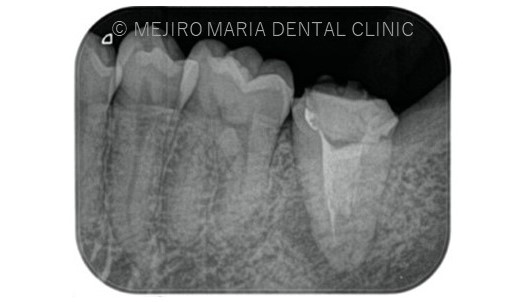

前医にて根管治療を終了したが、痛みと違和感に改善がないため来院された患者様です。前医では樋状根(といじょうこん)の為、これ以上の治療はできないと言われ、抜歯を勧められていました。

根尖性歯周炎は細菌が原因であるため、根管治療にてできる限り細菌を除去することが必要になります。しかしながら、樋状根(Cシェイプ)は根管の大部分が根内部でつながっている形態をしているため(写真2)洗浄が非常に困難です。

また、今回のような樋状根(Cシェイプ)は内側の隆起している部位(写真2赤丸部位)など、歯質が非常に薄い形態をしていることからむやみに削合を行うと穿孔(読み:せんこう パーフォレションともいわれ、歯に穴をあけてしまうことを指す)を起こしてしまう可能性も高くなります。

本症例においても、樋状根に対してマイクロスコープにて直視下にて、切削や超音波を使った化学的洗浄を十分に行いました。